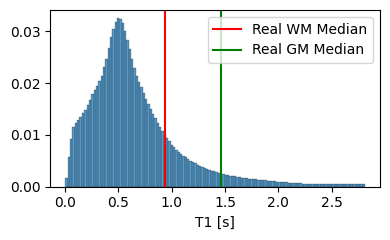

We set and based on the median of the property value distribution measured in real brain tissue [1], corresponding to a log-normal prior with a median of on T1 and a median of on T2.

3.1.2 Analysis of the Tissue Property Distribution

To ensure that our model can extrapolate to unseen modalities, it is crucial that the tissue property maps contain physically plausible values. In Figure 4, we compare the distribution of T1 and T2 values generated by our model to the average T1 and T2 values of white matter and grey matter in actual brain tissue. The results highlight the importance of the prior on the predicted T1 and T2 values, as it guides the model towards generating tissue properties that are, on average, more realistic. However, it is essential to note that the generated distribution includes tissue types beyond white matter and grey matter, such as cerebrospinal fluid and bones.